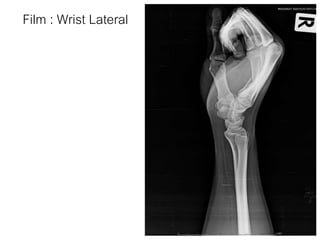

Film : Wrist Lateral

Film : WristLateral